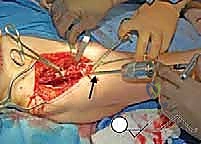

2. الشقوق الجراحية (Incisions)

يُجري الدكتور هطيف شقوقاً استراتيجية مصممة لتقليل الضرر العضلي وترك ندبات تجميلية صغيرة قدر الإمكان. يتم الوصول إلى العظام الثلاثة بعناية فائقة وتجنيب الأوعية الدموية الحساسة.

3. مرحلة القطع العظمي (The Three Osteotomies)

هنا تكمن عبقرية الإجراء. يتم استخدام مناشير جراحية دقيقة لعمل قطوع في:

* عظم الإسك (Ischium): العظم السفلي الخلفي للحوض.

* عظم العانة (Pubis): العظم الأمامي للحوض.

* عظم الحرقفة (Ilium): العظم العلوي العريض للحوض.

بمجرد اكتمال هذه القطوع الثلاثة، يصبح التجويف الحقي (الكوب) منفصلاً تماماً عن بقية الحوض، مع بقاء إمداداته الدموية سليمة.